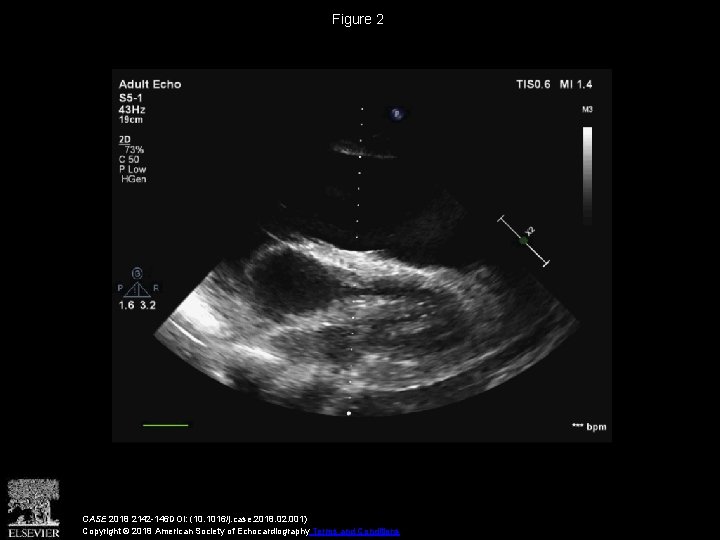

Figure 2 CASE 2018 2142 -146 DOI: (10. 1016/j. case. 2018. 02. 001) Copyright

Figure 2 CASE 2018 2142 -146 DOI: (10. 1016/j. case. 2018. 02. 001) Copyright © 2018 American Society of Echocardiography Terms and Conditions